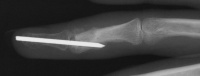

| Case 3. This 26 year old

woman presented with recurrent pain and swelling two years following

excision of an osteoid osteoma of the ring finger middle phalanx head.

Bone scan shows intense activity in this area, consistent with either

| The tumor was resected

using a dorsal tendon splitting exposure. |

| Debridement was continued

until normal counts were demonstrated . This left a thin

cortical shell which was reconstructed with a corticocancellous graft

from the distal radius. |